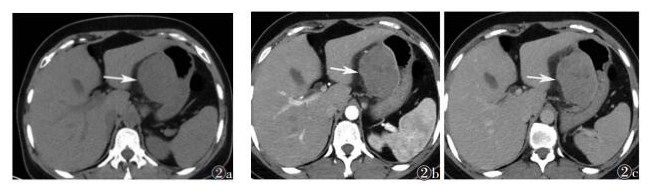

| 图 2 男,51岁 图 2a CT平扫示胃小弯侧类圆形软组织密度肿块影,腔外生长,胃壁侧可见局限性小凹陷,瘤体密度欠均,边界尚清(箭头) 图 2b 增强扫描动脉期轻度强化,其内见小片状低密度区(箭头) 图 2c 静脉期强化仍可见小片状低密度区(箭头) |

2.2 MSCT表现8例中,7例表现为圆形或类圆形肿块,其中1例边缘可见小凹陷;另1例肿块较大,边缘可见浅分叶。3例向腔内生长,2例向腔外生长,3例腔内外生长。平扫CT值30~60 HU,增强扫描:1例在动脉期明显均匀强化(图 1);2例肿块内部发现小片状低密度区,增强扫描强化不均匀(图 2);5例均呈均质密度,动脉期轻度强化,静脉期轻中度强化。1例伴胃周淋巴结肿大(图 3),病理证实肿大淋巴结为反应性增生,并非转移。所有患者均未发现钙化灶、出血、邻近结构侵犯及腹水等情况。